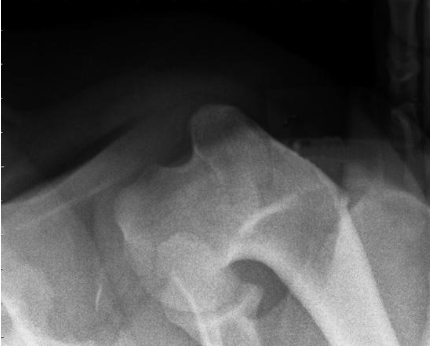

what radiographic view of the shoulder is shown?

skyline view